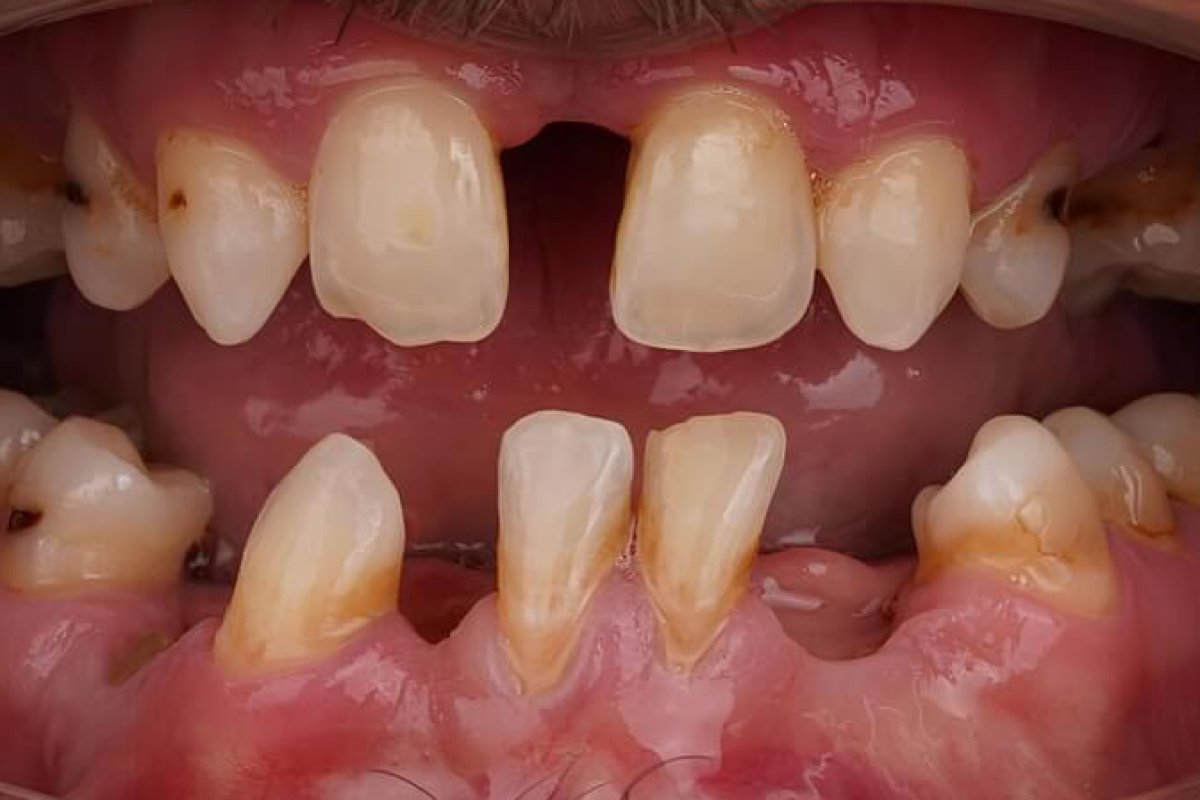

Before Before

Severely compromised dentition: multiple missing teeth (upper lateral incisor gap visible), heavy staining and calculus buildup, significant decay on multiple posterior teeth, crowding and tipping of lower anterior teeth, periodontal inflammation, severely worn and discolored enamel throughout.

Intraoral examination revealed generalised chronic periodontitis with active inflammation, six non-restorable teeth, rampant posterior caries, severe anterior wear and staining, and pathological migration of the lower incisors. Occlusal vertical dimension was significantly compromised. Radiographic review confirmed adequate residual bone volume in planned implant sites, with the exception of the upper left lateral region which required socket management prior to fixture placement.